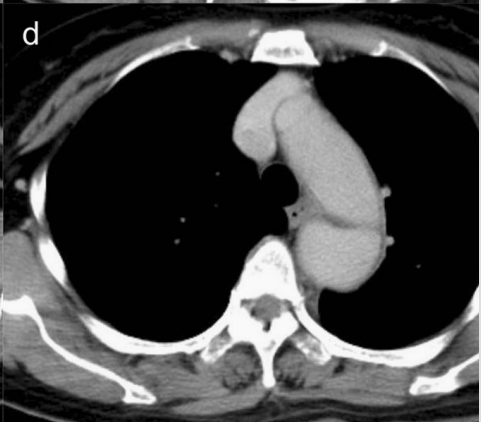

下图的胸部CT平扫,有什么大问题?

仔细一看,主动脉里面有线样高密度阴影!这个要高度警惕主动脉夹层!